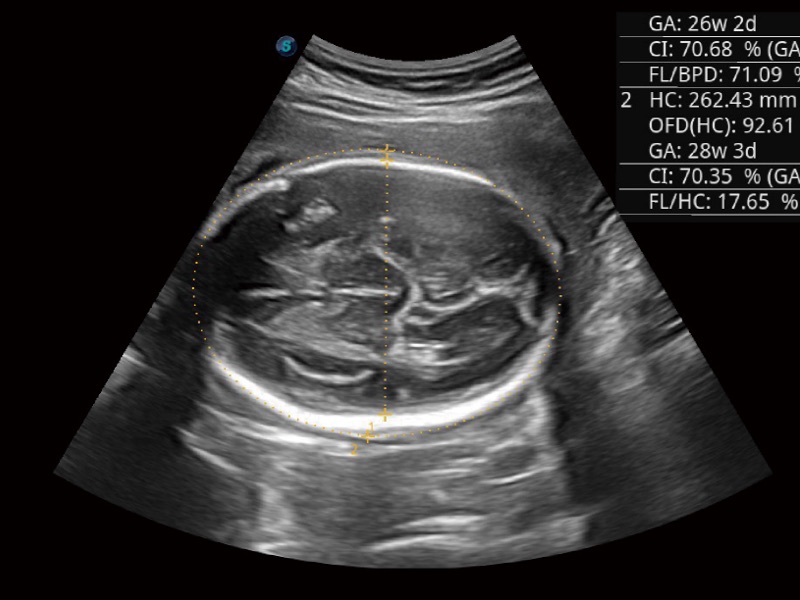

Auto OB Plus BPD y HC

• Obstetricia